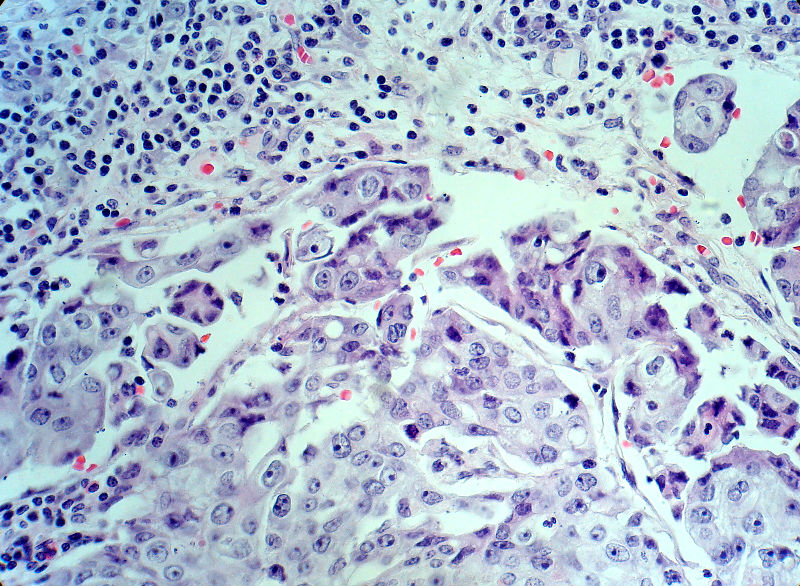

男,82岁,小肠穿孔紧急手术。

大体,小肠一段,长约60厘米,与粘膜面可见三个溃疡型肿物,肠系膜淋巴结肿大。

肿瘤呈巢片状分布,细胞大小相对一致,胞浆丰富,胞核呈细颗粒状,可见小核仁,血管较丰富,考虑神经内分泌肿瘤,加做免疫组化(Ki67、Syn、NSE、CgA、CD56)分级。

神经内分泌肿瘤,加做免疫组化(CKp、Ki67、Syn、NSE、CgA、CD56)分级。